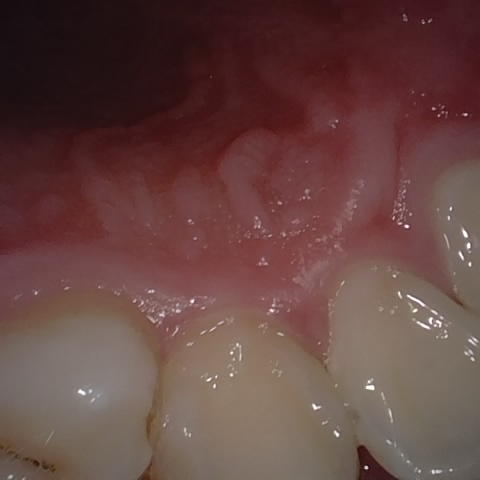

Annotated as "Good"